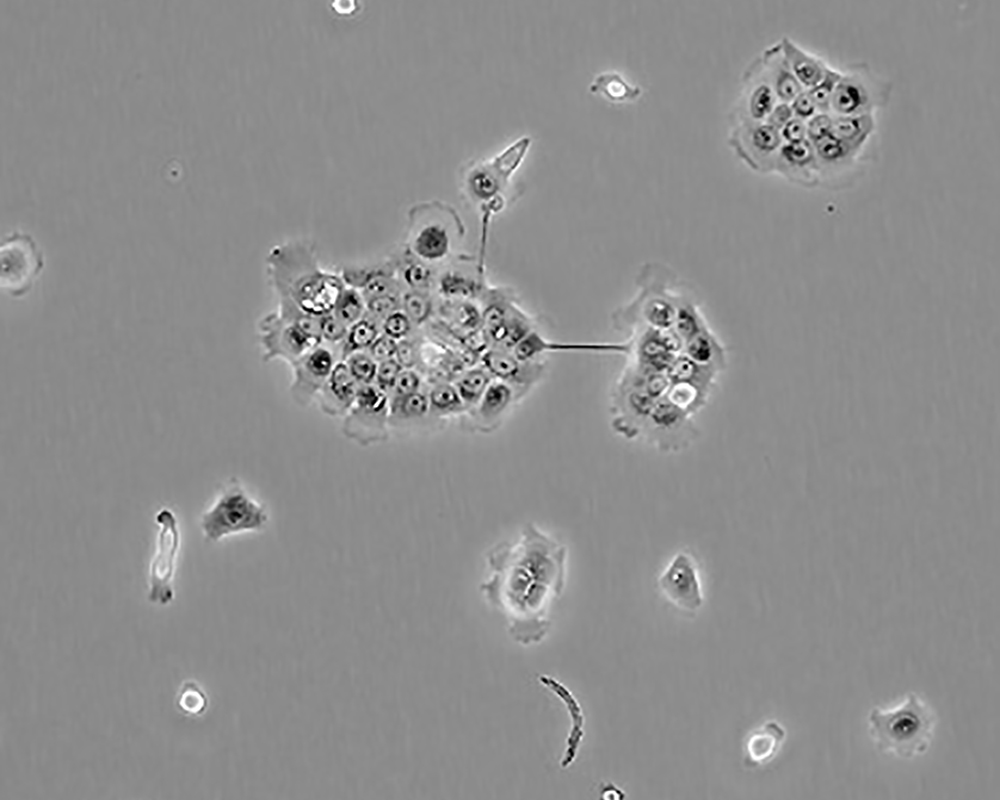

BxPC-3(BxPC3)

產(chǎn)品名稱 BxPC-3(BxPC3)

中文名稱 人原位胰腺腺癌細(xì)胞

組織來(lái)源 胰腺導(dǎo)管腺癌;女性

生長(zhǎng)特性 adherent

形態(tài)特征 epithelial

細(xì)胞描述 The cells do not express the cystic fibrosis transmembrane conductance regulator(CFTR). A CFTR positive pancreatic line, Capan-1 is available.